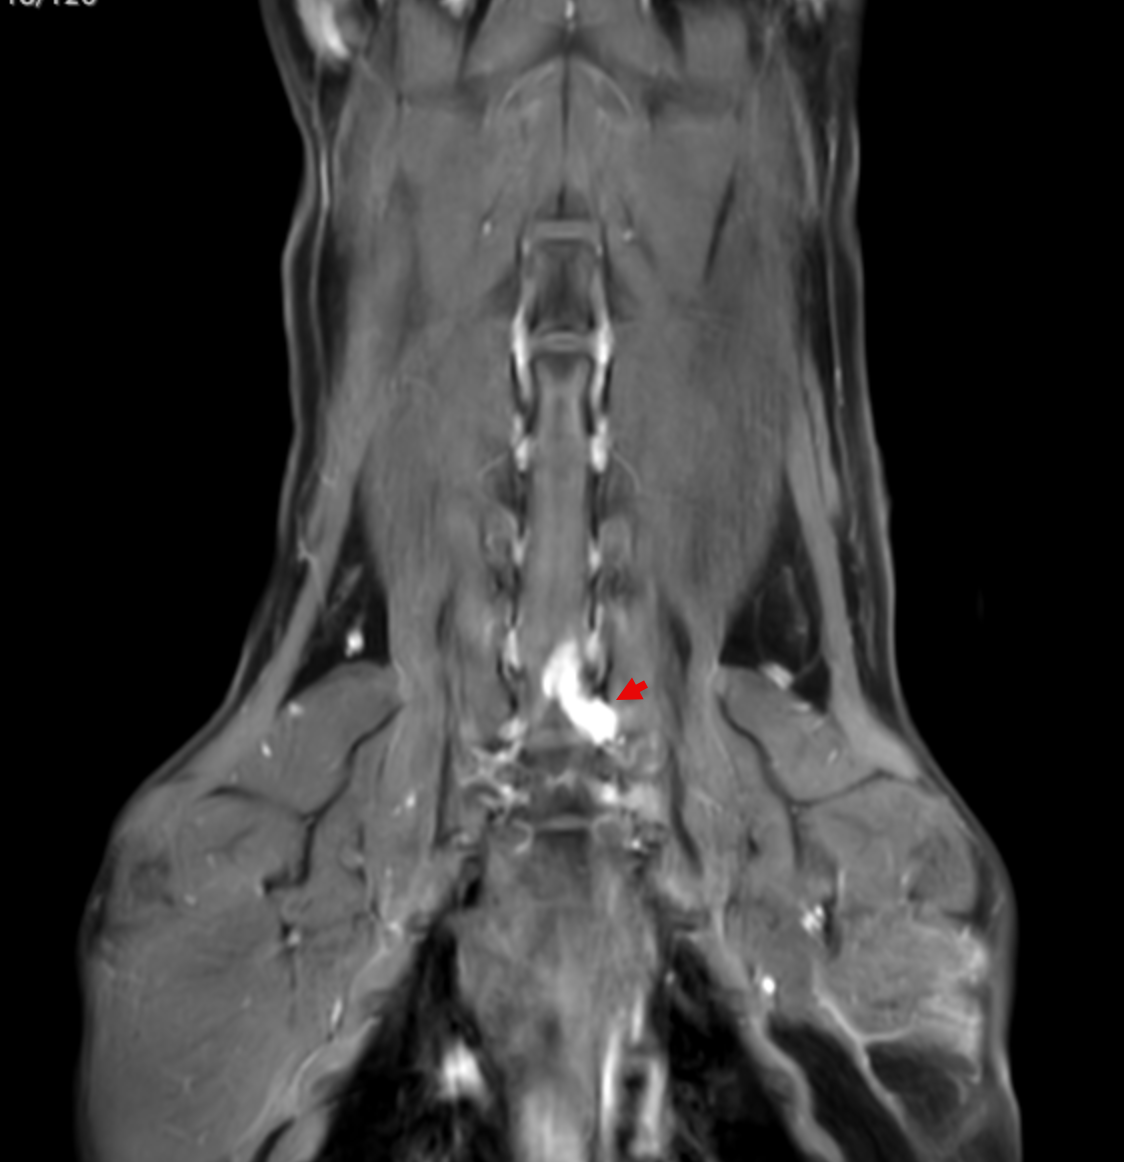

Image 5. Dorsal post-contrast MRI of the cervical spine and thoracic inlet demonstrating a contrast-enhancing lesion associated with the left-sided C7–T1 nerve roots extending into the brachial plexus.

MRI revealed a clinically significant and previously undetected diagnosis (Images 5-7):

Primary Diagnosis: Nerve Sheath Tumor

• Contrast-enhancing mass involving the left C7, C8, and T1 nerve roots

• Extension from the spinal canal through the intervertebral foramen into the axilla and brachial plexus

• Severe spinal cord compression with displacement

• Expansion of the C7–T1 neural foramen

• Associated neurogenic muscle atrophy of the left forelimb (triceps)

Additional Findings

In other words, what appeared to be a routine lameness case was actually being driven by a much more complex, and previously hidden, neurologic condition.

Ginger’s lameness was not caused by arthritis.

Instead, it was the result of a nerve sheath tumor affecting the brachial plexus, leading to:

• Pain originating from the nerve roots

• Loss of limb function

• Muscle atrophy due to denervation